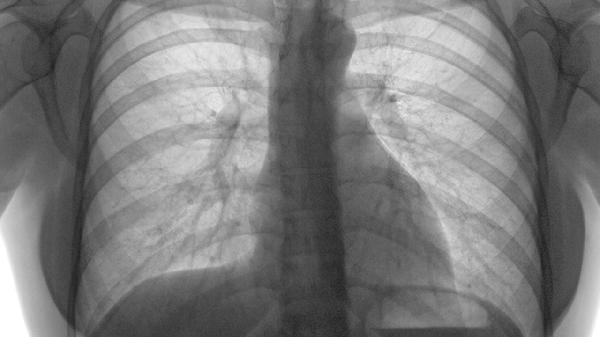

肺栓塞的保健護(hù)理

肺栓塞患者可通過調(diào)整飲食、適度運(yùn)動(dòng)、規(guī)范用藥、心理疏導(dǎo)、定期復(fù)查等方式進(jìn)行保健護(hù)理。肺栓塞通常由靜脈血栓形成、長(zhǎng)期臥床、手術(shù)創(chuàng)傷、惡性腫瘤、凝血功能異常等因素引起。